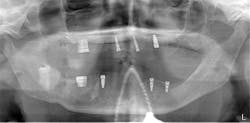

After the fabrication of full upper and lower immediate dentures, the patient underwent extraction of the remaining teeth and the placement of eight immediate dental implants (Hahn Tapered Implants, Glidewell; figure 8).

Figure 8: Post-op panorex